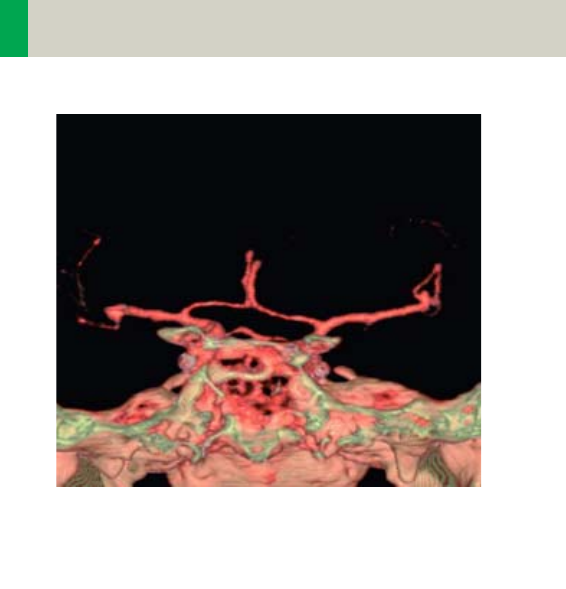

Vascular 360

•Overview 360

- General Hints 363

- Head Kernels 364

- Body Kernels 365

•Scan Protocols 366

- HeadAngio/

HeadAngio06s 366

- HeadAngioVol 370

-CarotidAngio/

CarotidAngio06s 372

- CarotidAngioVol 376